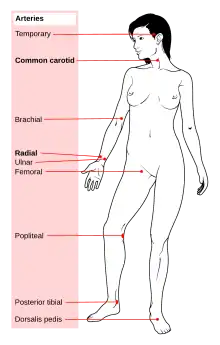

In medicine, a pulse represents the tactile arterial palpation of the cardiac cycle (heartbeat) by trained fingertips. The pulse may be palpated in any place that allows an artery to be compressed near the surface of the body, such as at the neck (carotid artery), wrist (radial artery), at the groin (femoral artery), behind the knee (popliteal artery), near the ankle joint (posterior tibial artery), and on foot (dorsalis pedis artery). Pulse (or the count of arterial pulse per minute) is equivalent to measuring the heart rate. The heart rate can also be measured by listening to the heart beat by auscultation, traditionally using a stethoscope and counting it for a minute. The radial pulse is commonly measured using three fingers. This has a reason: the finger closest to the heart is used to occlude the pulse pressure, the middle finger is used get a crude estimate of the blood pressure, and the finger most distal to the heart (usually the ring finger) is used to nullify the effect of the ulnar pulse as the two arteries are connected via the palmar arches (superficial and deep). The study of the pulse is known as sphygmology.

Common palpable sites

Sites can be divided into peripheral pulses and central pulses. Central pulses include the carotid, femoral, and brachial pulses.[11]

Upper limb

- Axillary pulse: located inferiorly of the lateral wall of the axilla

- Brachial pulse: located on the inside of the upper arm near the elbow, frequently used in place of carotid pulse in infants (brachial artery)

- Radial pulse: located on the lateral of the wrist (radial artery). It can also be found in the anatomical snuff box.

- Ulnar pulse: located on the medial of the wrist (ulnar artery).

Lower limb

- Femoral pulse: located in the inner thigh, at the mid-inguinal point, halfway between the pubic symphysis and anterior superior iliac spine (femoral artery).

- Popliteal pulse: Above the knee in the popliteal fossa, found by holding the bent knee. The patient bends the knee at approximately 124°, and the health care provider holds it in both hands to find the popliteal artery in the pit behind the knee (Popliteal artery).

- Dorsalis pedis pulse: located on top of the foot, immediately lateral to the extensor of hallucis longus (dorsalis pedis artery).

- Tibialis posterior pulse: located on the medial side of the ankle, 2 cm inferior and 2 cm posterior to the medial malleolus (posterior tibial artery). It is easily palpable over Pimenta's Point.

Head and neck

- Carotid pulse: located in the neck (carotid artery). The carotid artery should be palpated gently and while the patient is sitting or lying down. Stimulating its baroreceptors with low palpitation can provoke severe bradycardia or even stop the heart in some sensitive persons. Also, a person's two carotid arteries should not be palpated at the same time. Doing so may limit the flow of blood to the head, possibly leading to fainting or brain ischemia. It can be felt between the anterior border of the sternocleidomastoid muscle, above the hyoid bone and lateral to the thyroid cartilage.

- Facial pulse: located on the mandible (lower jawbone) on a line with the corners of the mouth (facial artery).

- Temporal pulse: located on the temple directly in front of the ear (superficial temporal artery).